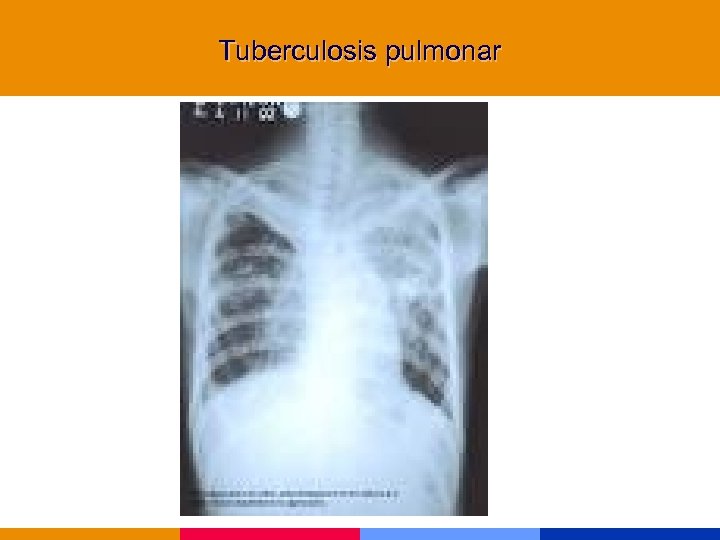

Tuberculosis § La infección por HIV predispone a TBC, y ésta deteriora la evolución de la infección por HIV § Presentación clínica depende del nivel de inmunocompromiso • CD 4 >300 mm 3 similar a huésped normal con fiebre, tos productiva, hemoptisis, pérdida de peso y cavitación • CD 4 <200 mm 3 atípca con frecuente compromiso extrapulmonar, enfermedad miliar y ausencia de tos.

Tuberculosis § La infección por HIV predispone a TBC, y ésta deteriora la evolución de la infección por HIV § Presentación clínica depende del nivel de inmunocompromiso • CD 4 >300 mm 3 similar a huésped normal con fiebre, tos productiva, hemoptisis, pérdida de peso y cavitación • CD 4 <200 mm 3 atípca con frecuente compromiso extrapulmonar, enfermedad miliar y ausencia de tos.

Tuberculosis § PPD positiva sólo en 30 a 50% de los pacientes. § Rx tórax: opacidades intersticiales o lobares, perihiliares. § Esputo: sensibilidad similar a pacientes HIV negativos § Tratamiento empírico inicial: se acepta en espera de resultados de cultivos.

Tuberculosis § PPD positiva sólo en 30 a 50% de los pacientes. § Rx tórax: opacidades intersticiales o lobares, perihiliares. § Esputo: sensibilidad similar a pacientes HIV negativos § Tratamiento empírico inicial: se acepta en espera de resultados de cultivos.

Tuberculosis pulmonar

Tuberculosis pulmonar

Tuberculosis pulmonar

Tuberculosis pulmonar